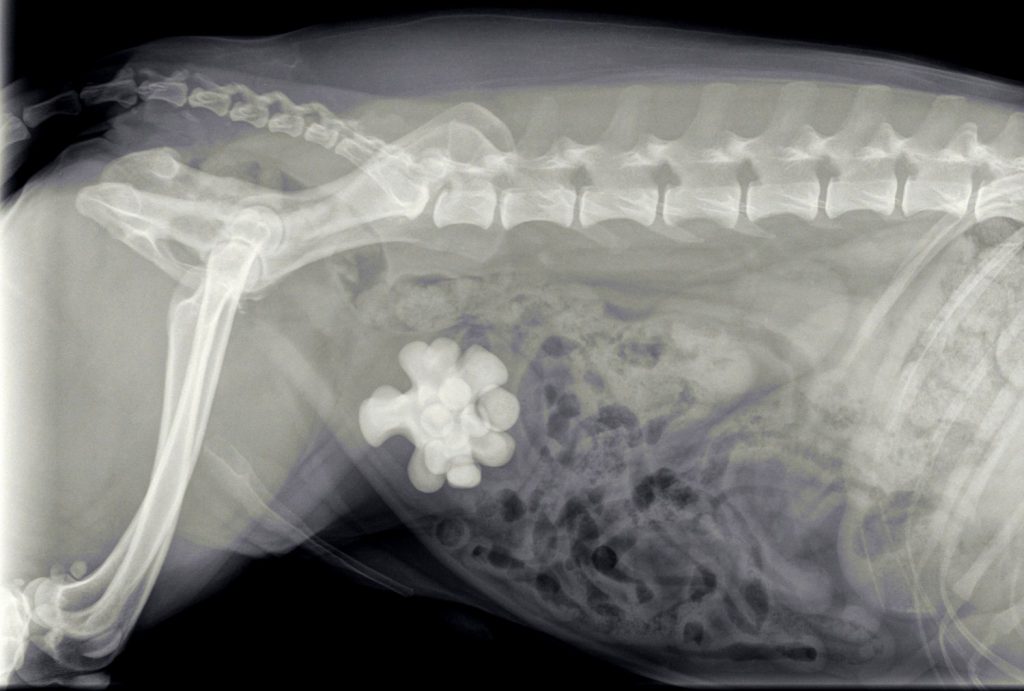

Spike is een zwarte kruising reu uit Rijswijk die in augustus bij de dierenarts op consult kwam vanwege het laten lopen van urine. De urine stonk ook behoorlijk en Spike lekte overal. Bij het urine-onderzoek viel onder andere op dat er zeer veel ontstekingscellen in de urine aanwezig waren, maar geen gruis. Bij het klinisch onderzoek voelde we in de omgeving van de blaas een structuur, die daar niet hoorde te zitten. In overleg met de eigenaar zijn we overgegaan tot het maken van röntgenfoto’s.

Spike had last van blaasstenen, terwijl we daar in het urine-onderzoek geen aanwijzingen voor hadden gevonden. Omdat Spike al bijna 10 jaar oud was hebben we met een bloedonderzoek eerst zijn nieren en lever getest. Vervolgens hebben we Spike geopereerd om de stenen te verwijderen.

De grote verassing kwam met het feit dat het niet om een verzameling van kleine steentjes ging, zoals meestal. In dit geval ging het om één hele grote steen en meerdere kleinere.